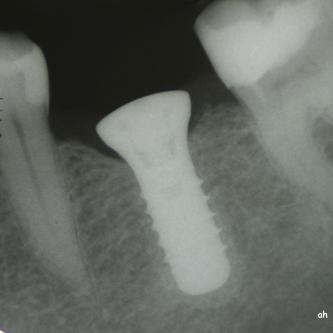

Exemple 2: Un implant remplaçant la racine d'une molaire inférieure gauche.

Exemple 2: La couronne en céramique scellée sur cet implant.